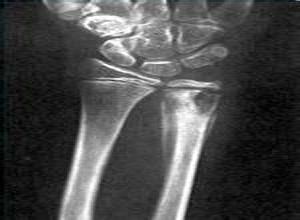

早期的骨结核多为偶然的关节疼痛,逐渐加重并转为经常疼痛,活动时疼痛加重,有压痛,疼痛可放射至其它部位,有的患者也可能没有疼痛症状,由于对骨质破坏和附近软组织肿胀而形成的脓肿刺激和压迫肌肉神经,使局部血液循环不畅,疼痛便是这种病机的神经反射,往往在本病的中后期出现。有的患者没有产生上述病机,或程度轻微,则不出现疼痛及很少疼痛。>>>我得了骨结核十分的疼痛,怎么办?